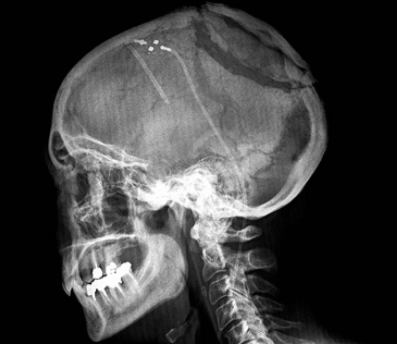

儿童由于颅骨未发育成熟,是脆弱的,加上脑脊髓肿瘤一般位置深在,手术需小心,尽量避免损伤正常的脑组织。在西方发达国家,为了降低切除或损伤大脑重要部分的风险,通常使用不同的技术来进行辅助,如:

功能性核磁共振成像:在手术之前,这种类型的成像测试可以用来定位大脑的特定功能。这可以用来帮助在操作期间保护该区域。

术中皮层刺激(皮层映射):在手术中,神经外科医生通常可以通过电刺激和监测反应来检测肿瘤内部和周围的大脑区域的功能。这将显示这些区域是否控制着重要的功能,帮助外科医生避免它们。

术中成像:在某些情况下,外科医生使用在手术中不同时间拍摄的MRI(或其他)图像来显示任何剩余肿瘤的位置。这可能会使一些脑瘤被更顺利、更广泛地切除。